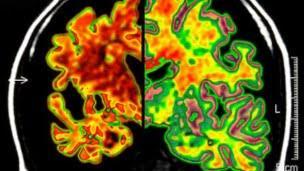

Los participantes habían sido sometidos a pruebas cognitivas para medir capacidades como control de atención y memoria, y a escáneres cerebrales para medir los cambios cerebrales.

No se conoce con claridad cuáles son los mecanismos que subyacen a esta protección, pero tal como explica la doctora Bialystok, el bilingüismo podría ser un factor ambiental que está contribuyendo a la llamada reserva cognitiva del cerebro.

Esta reserva cognitiva también puede postergar la aparición de los síntomas en quienes sufren demencia.

Según la investigadora, para poder seleccionar un lenguaje apropiado el individuo debe hacer uso de regiones del cerebro que son esenciales para la atención general y el control congitivo.

El uso de esas redes de control congitivo para el procesamiento del lenguaje bilingüe puede reconfigurar y fortalecer estas regiones, quizás mejorando la flexibilidad mental, que es la capacidad de adaptarse a los continuos cambios y procesar la información de forma más eficiente, explican los autores.

"Nuestra conclusión es que la experiencia de manejar la atención a dos idiomas, que puede durar toda la vida, reorganiza redes específicas del cerebro creando una base más efectiva para el control ejecutivo y para un mejor rendimiento cognitivo a lo largo de la vida" afirma la doctora Bialystok.